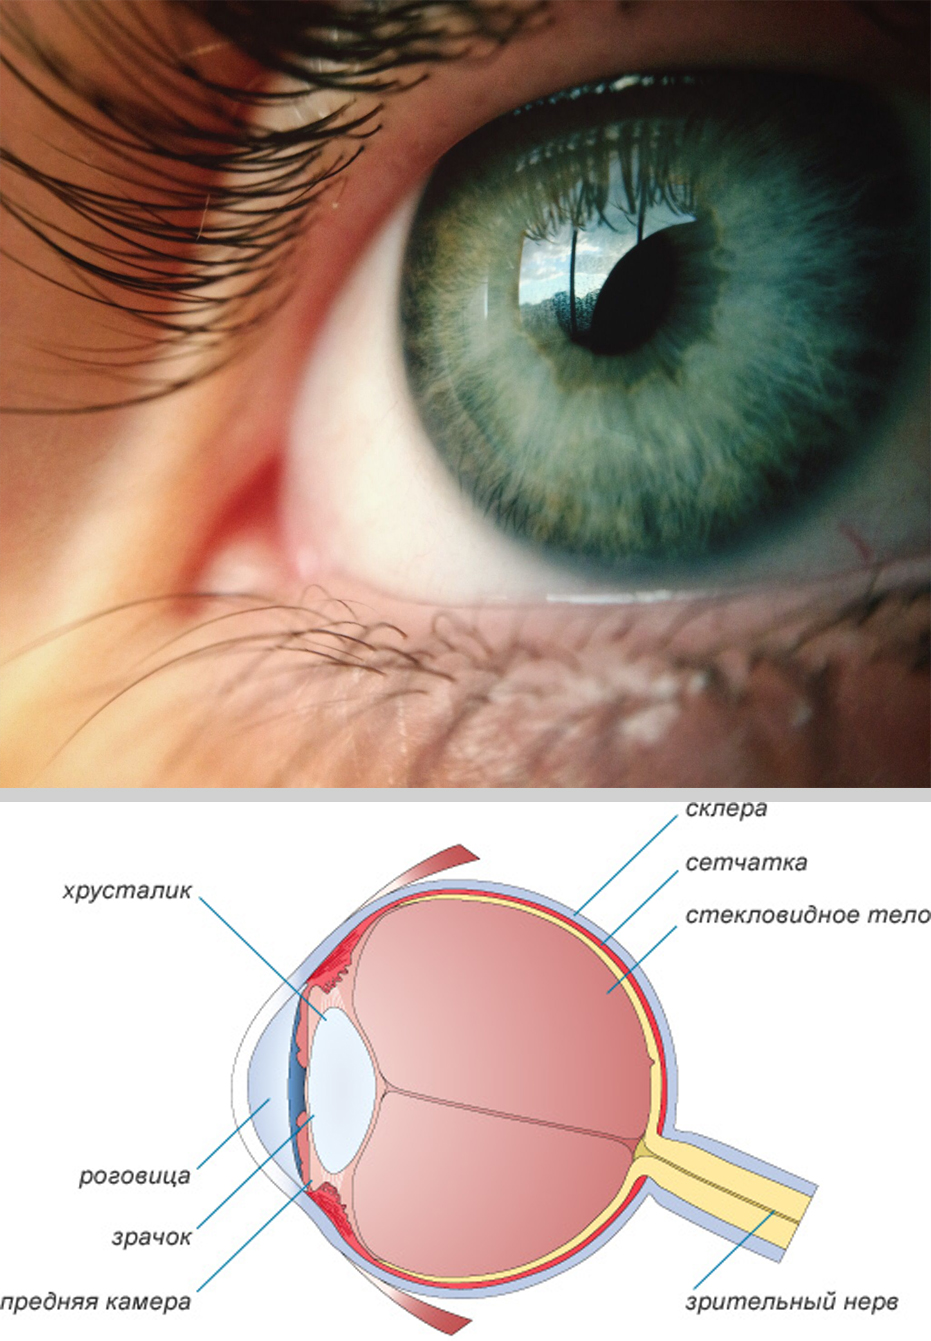

Изображения и анатомия сетчатки глаза